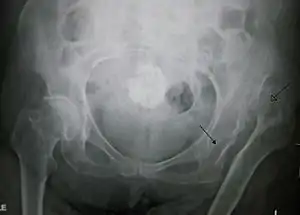

Displasia de desenvolvimento da anca é uma malformação da articulação da anca em que o acetábulo não reveste completamente a cabeça do fémur, o que faz aumentar o risco de luxação.[1] A displasia da anca pode estar presente desde o nascimento ou desenvolver-se no início da vida.[1] No entanto, em crianças com menos de um ano de idade geralmente não se manifestam sintomas.[3] Em alguns casos, uma das pernas pode ser mais curta do que a outra.[1] A anca esquerda é afetada com maior frequência do que a anca direita.[3] Se não for tratada, é possível que mais tarde ocorram complicações como artrite, coxear e dores no fundo das costas.[3]